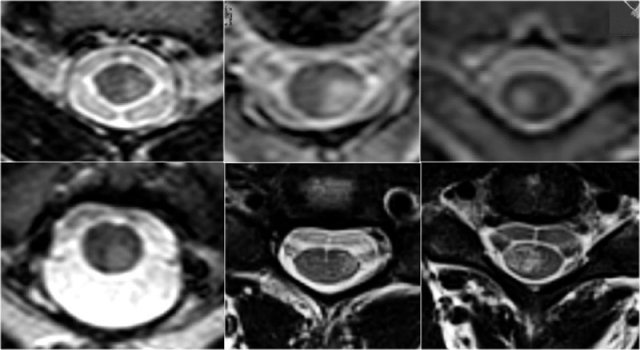

Transverse images are very helpful in the differential diagnosis.

You need high resolution images.

Look for how much is involved (both halves or not), which part is involved and what is the form of the involvement.

MS typically is triangular in shape and mostly located dorsally or laterally.

However MS can look like anything and may uncommonly involve the whole transverse diameter or only the anterior part. - Ischemia as a result of arterial infarction is typically located in the anterior parts, but may involve the entire transverse diameter.

- Transverse myelitis and Neuromyelitis optica typically involve the whole cord.

On transverse images MS lesions typically have a round or triangular shape and are located posteriorly or laterally.

MS is the great mimicker and can also be located anteriorly like in this patient who has a lesion in the typical location (blue arrow) but also a lesion ventrally in the cord (red arrow).

On the transverse image a typical triangular shaped dorsal lesion is seen.

Notice the high signal ventrally in the chord, which is typical for arterial infarction.

On transverse images a typical snake-eye appearance can be seen.